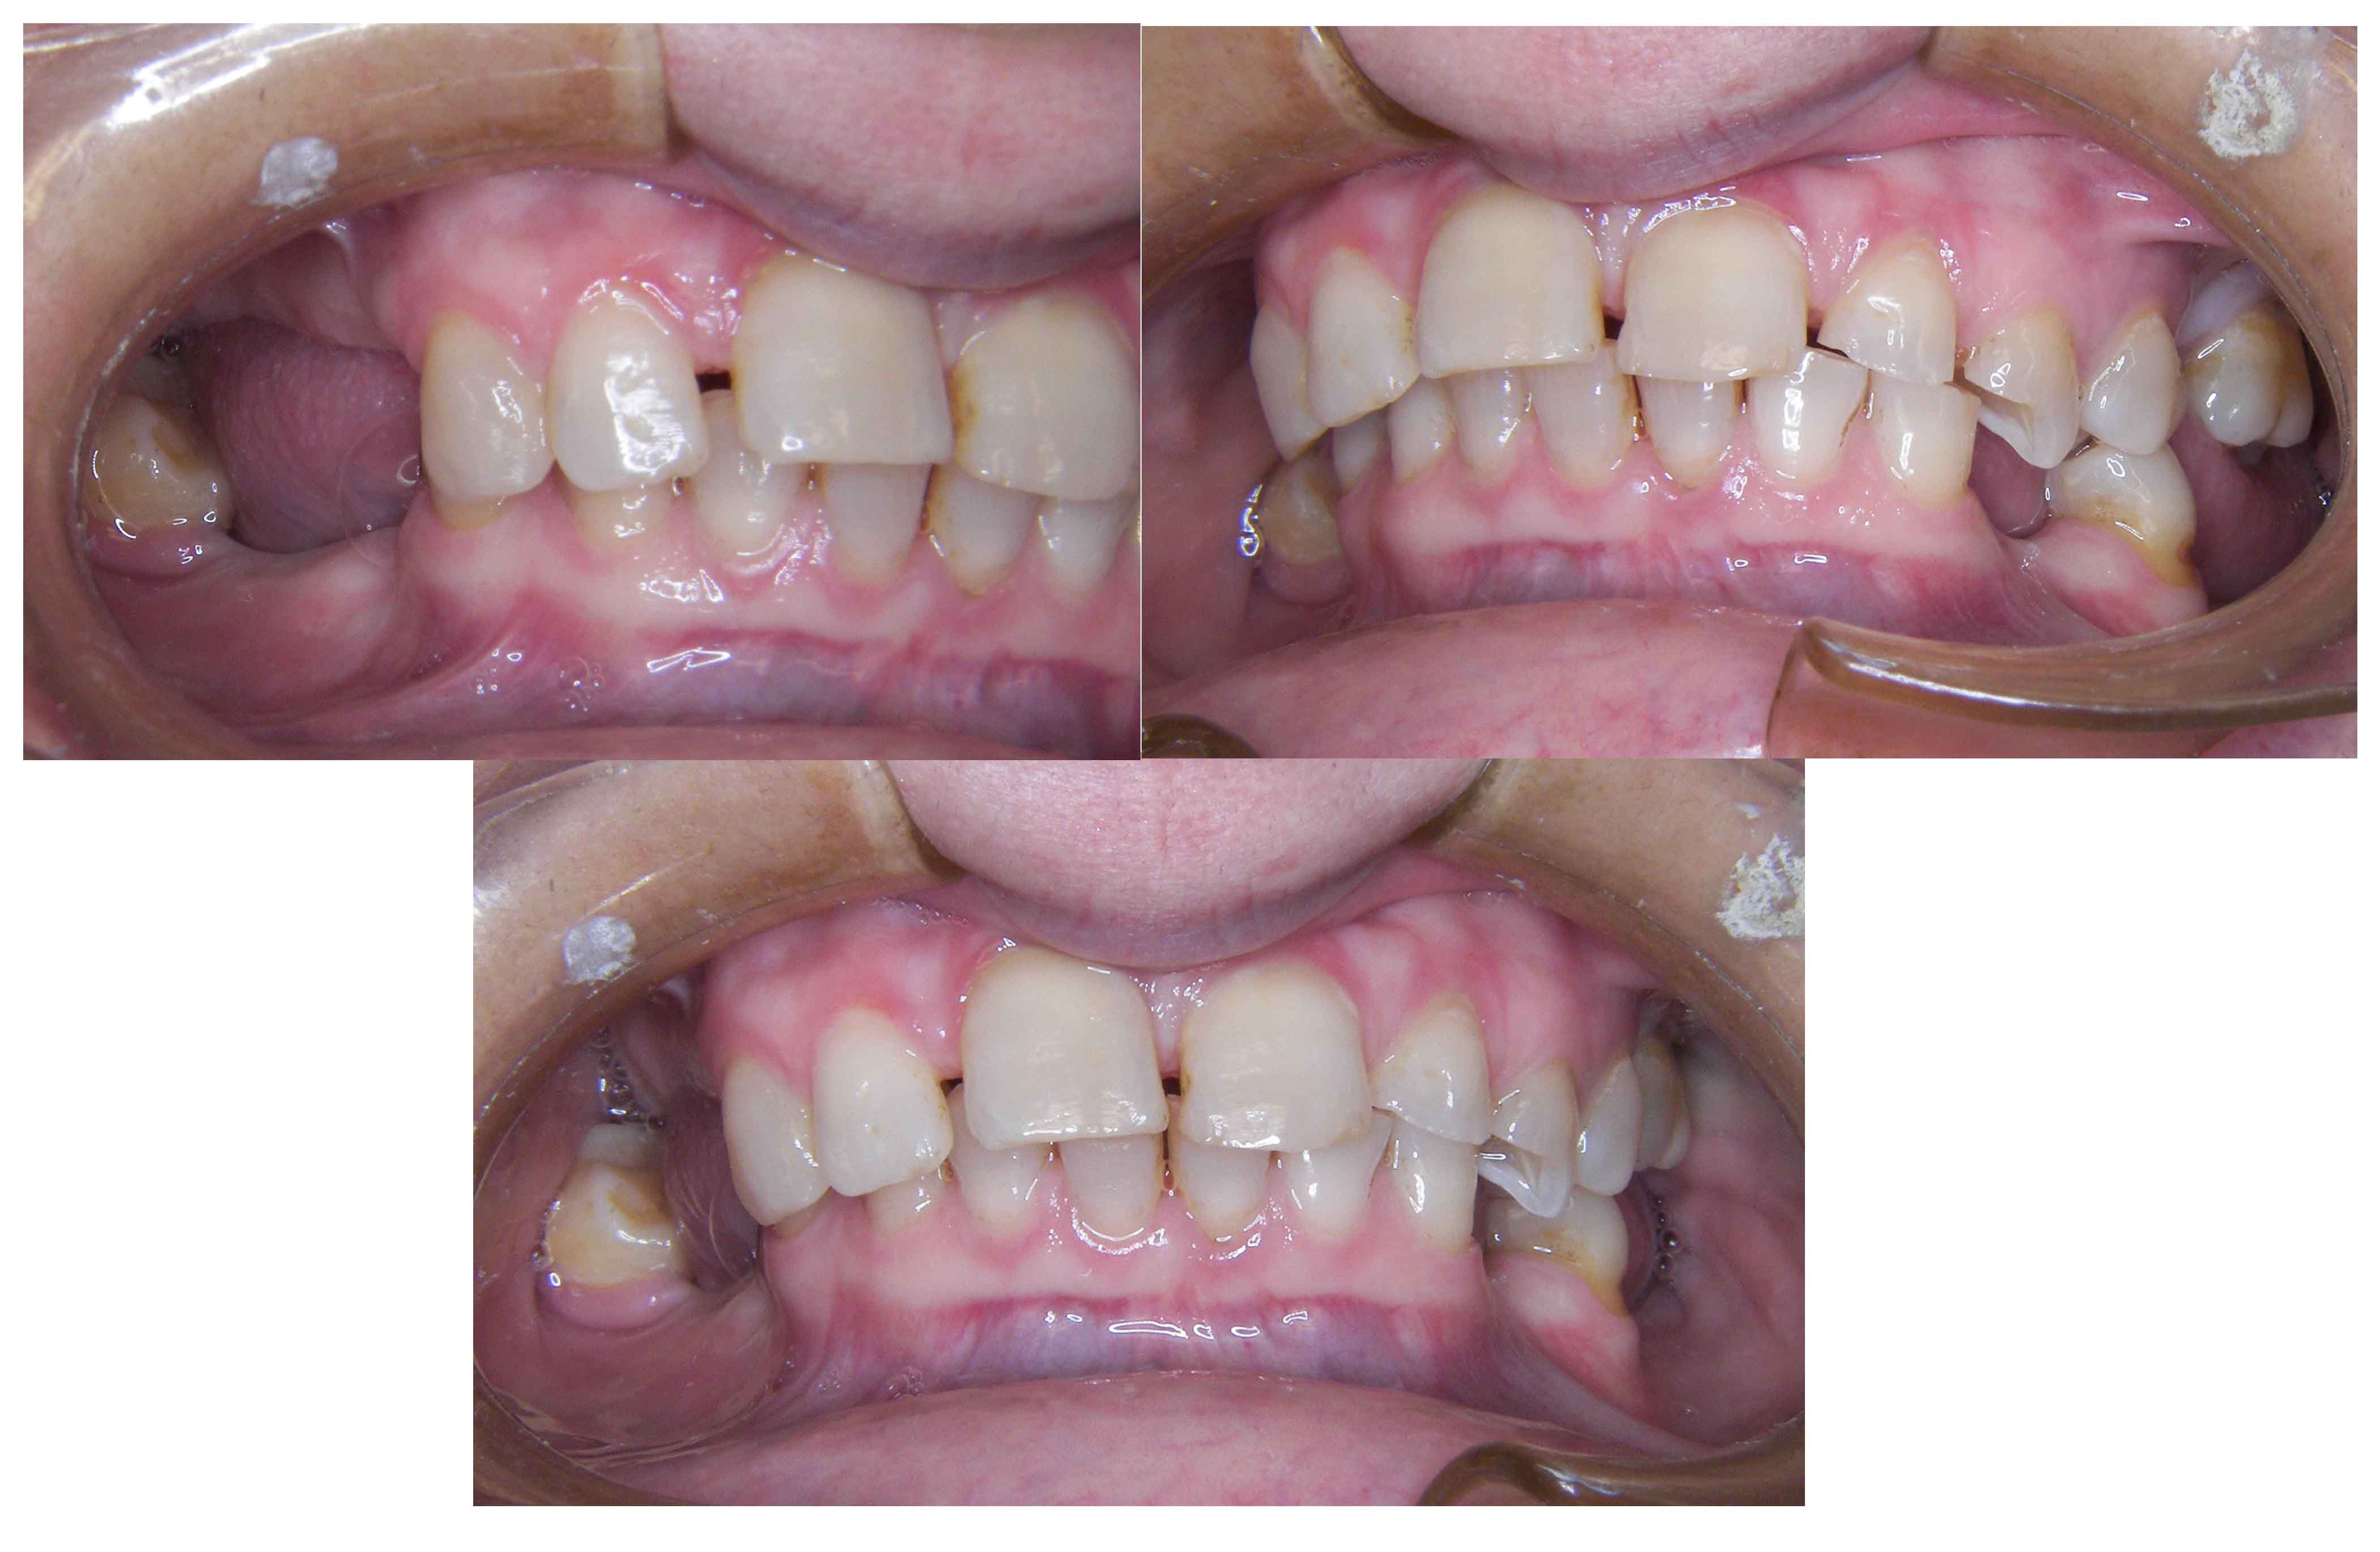

Patient with limited functions and serious aesthetics problems.

Complex Rehabilitation – The Treatment:

The natural teeth that had a good prognosis were kept and the ones that needed their position changed were moved by a fixed orthodontic brace.

Afterward a surgery was made to place some implants. The treatment was finalized by placing the ceramic crowns over the implants and teeth.